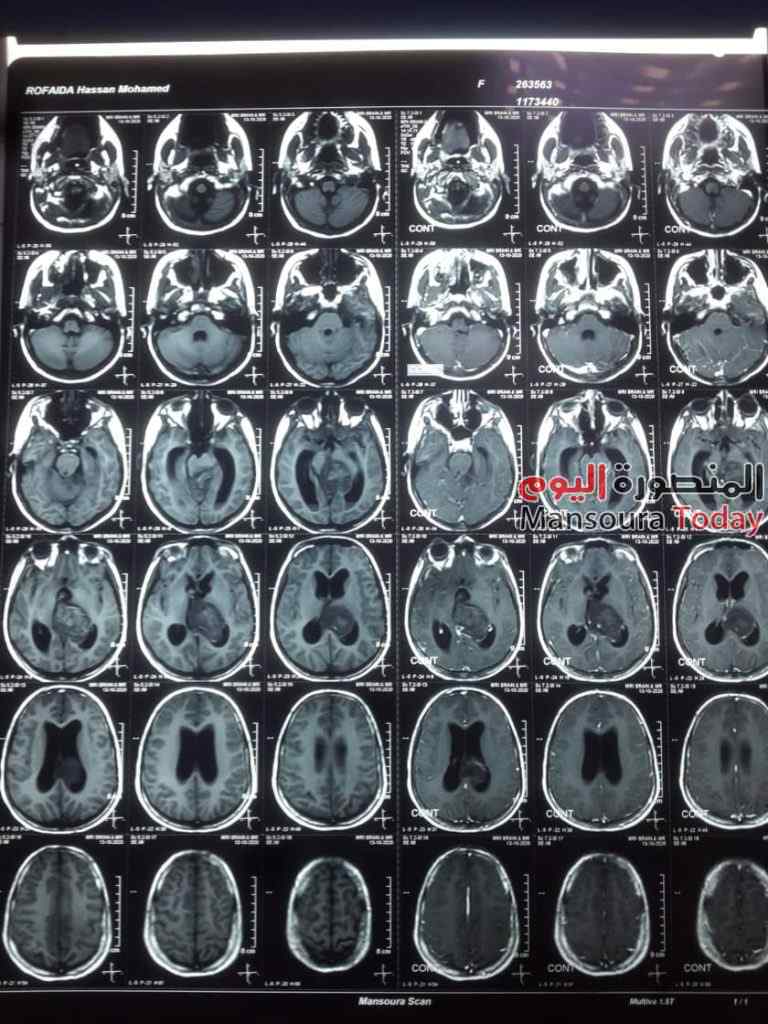

أعلن اليوم الدكتور سعد مكى وكيل وزارة الصحة بالدقهلية عن انجاز جديد لصحة الدقهلية، حيث نجح فريق طبي فى سابقة هي الأولى من نوعها فى مستشفيات وزارة الصحة بإنقاذ حياة طفلة تبلغ من العمر 11 عاما كانت تعانى من نزيف ببطينات المخ ادى الى تدهور شديد فى درجة الوعى لارتفاع ضغط السائل النخاعى على جذع المخ ، و تم التدخل الجراحي العاجل من الفريق الطبى وعمل الجراحة بطريقة بسيطة باستخدام جهاز ( CVP) بتحويل مسار السائل تحت فروة الرأس ventricluosubgaleal shunting وقد استغرقت العمليه حوالي خمس ساعات ،. وهي تعد من العمليات المتقدمة ذات المهارة الخاصة. الجدير بالذكر أن المعتاد فى السابق في مثل هذه الحالات ان يتم تركيب صمام مخى بريتونى دائم مما قد يؤدى الى مضاعفات فى تلك الحالات او تركيب صمام لخارج المخ فى جهاز تجميع خارجى قد يؤدى إلى التهابات بالسحايا المخية .